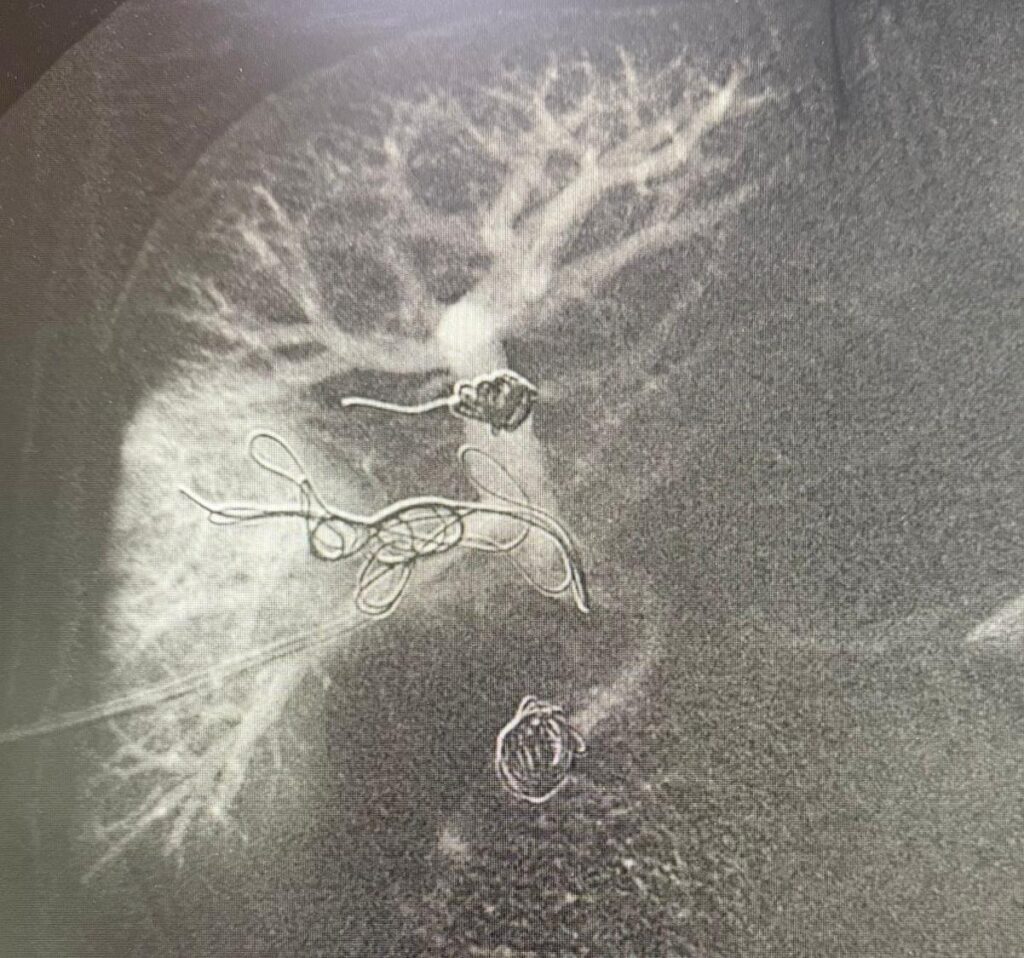

A intervenção foi conduzida pelos cirurgiões vasculares e endovasculares Romulo Bizare e Silfayner Dias e consistiu na realização da embolização da veia porta, a principal veia do fígado, por meio de punção trans-hepática percutânea guiada por ultrassom, técnica considerada de alta complexidade.

Como parte deste preparo, foi realizada a punção trans-hepática dos ramos portais direitos, seguida da embolização. Durante o procedimento, são introduzidos materiais específicos, como molas e partículas, nas veias do fígado, com o objetivo de interromper o fluxo sanguíneo na área afetada.

Esse processo faz com que o lobo direito, comprometido pela doença, reduza de tamanho, enquanto o lobo esquerdo, saudável, passe a crescer e se fortalecer. Com isso, cria-se uma condição mais segura para a realização futura da hepatectomia parcial.

O procedimento foi executado na sala de hemodinâmica, por meio de uma punção realizada na região do abdômen guiada por ultrassom e utilizando instrumentos de alta precisão.